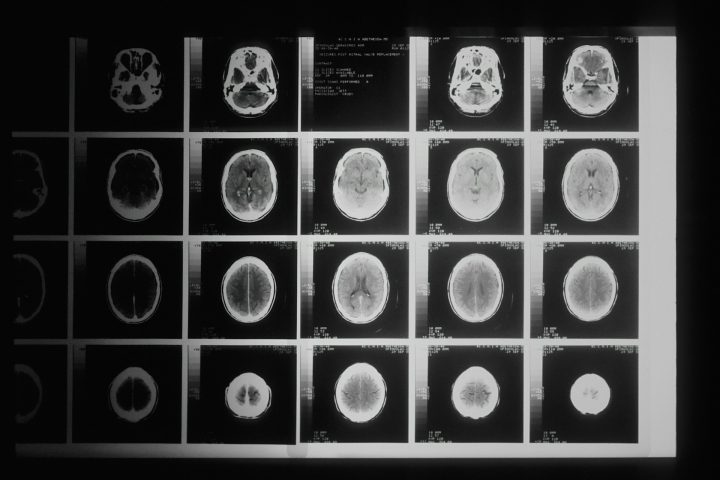

Homem que “morreu” por 7 segundos conta o que viu